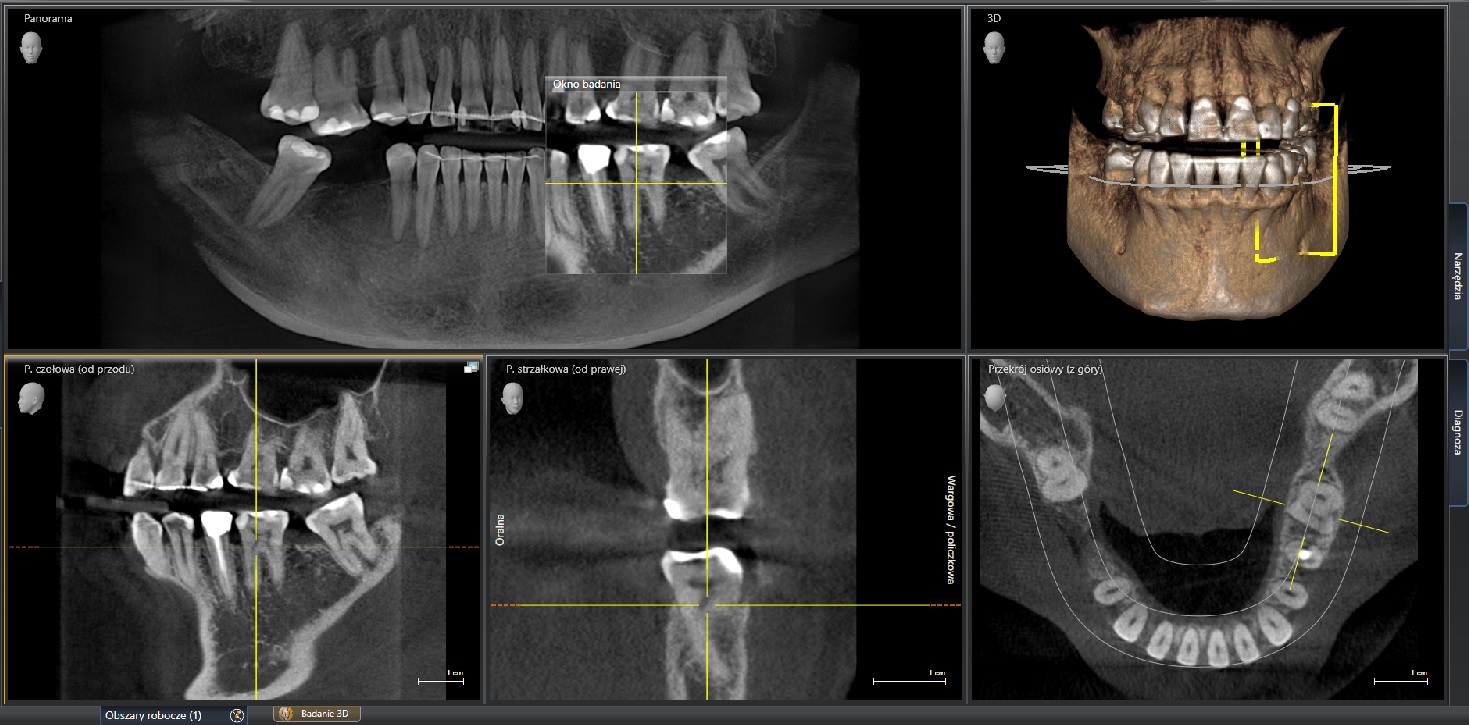

Tomograf Sirona ORTHOPHOS XG 3D

Tomograf Sirona ORTHOPHOS XG 3D to Urządzenie charakteryzujące się precyzyjnym systemem pozycjonowania pacjenta za pomocą linii laserowych i zautomatyzowanych programów, co jest kluczowe dla uzyskania powtarzalnych i wolnych od artefaktów obrazów.

Wykorzystuje technologię MARS (Metal Artifact Reduction Software) do minimalizacji zakłóceń powodowanych przez metalowe wypełnienia lub uzupełnienia protetyczne, co poprawia jakość diagnozy. Obrazy 3D charakteryzują się wysoką rozdzielczością.

Obrazy są przetwarzane i analizowane w dedykowanym oprogramowaniu Sidexis 4, które umożliwia zaawansowaną obróbkę, pomiary i planowanie leczenia.